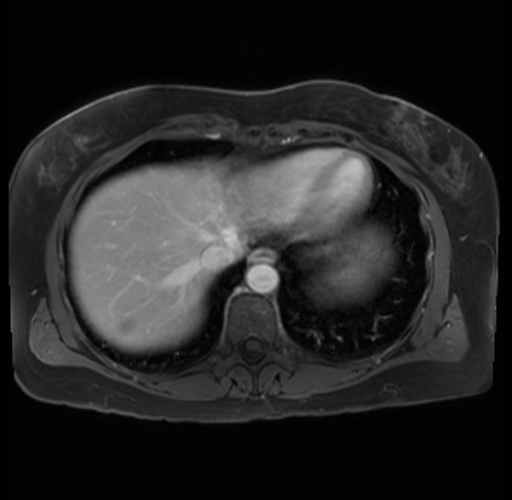

Imaging Analysis

Look through the patient's CT scan to identify any areas of concern for the necessary procedure.

Based on your CT findings, which issue(s) are present and would give reason for "planned slowing down moment(s)" in this case?

Considering a standard distal pancreatectomy procedure, what step(s) of the operation would you do differently in this case?